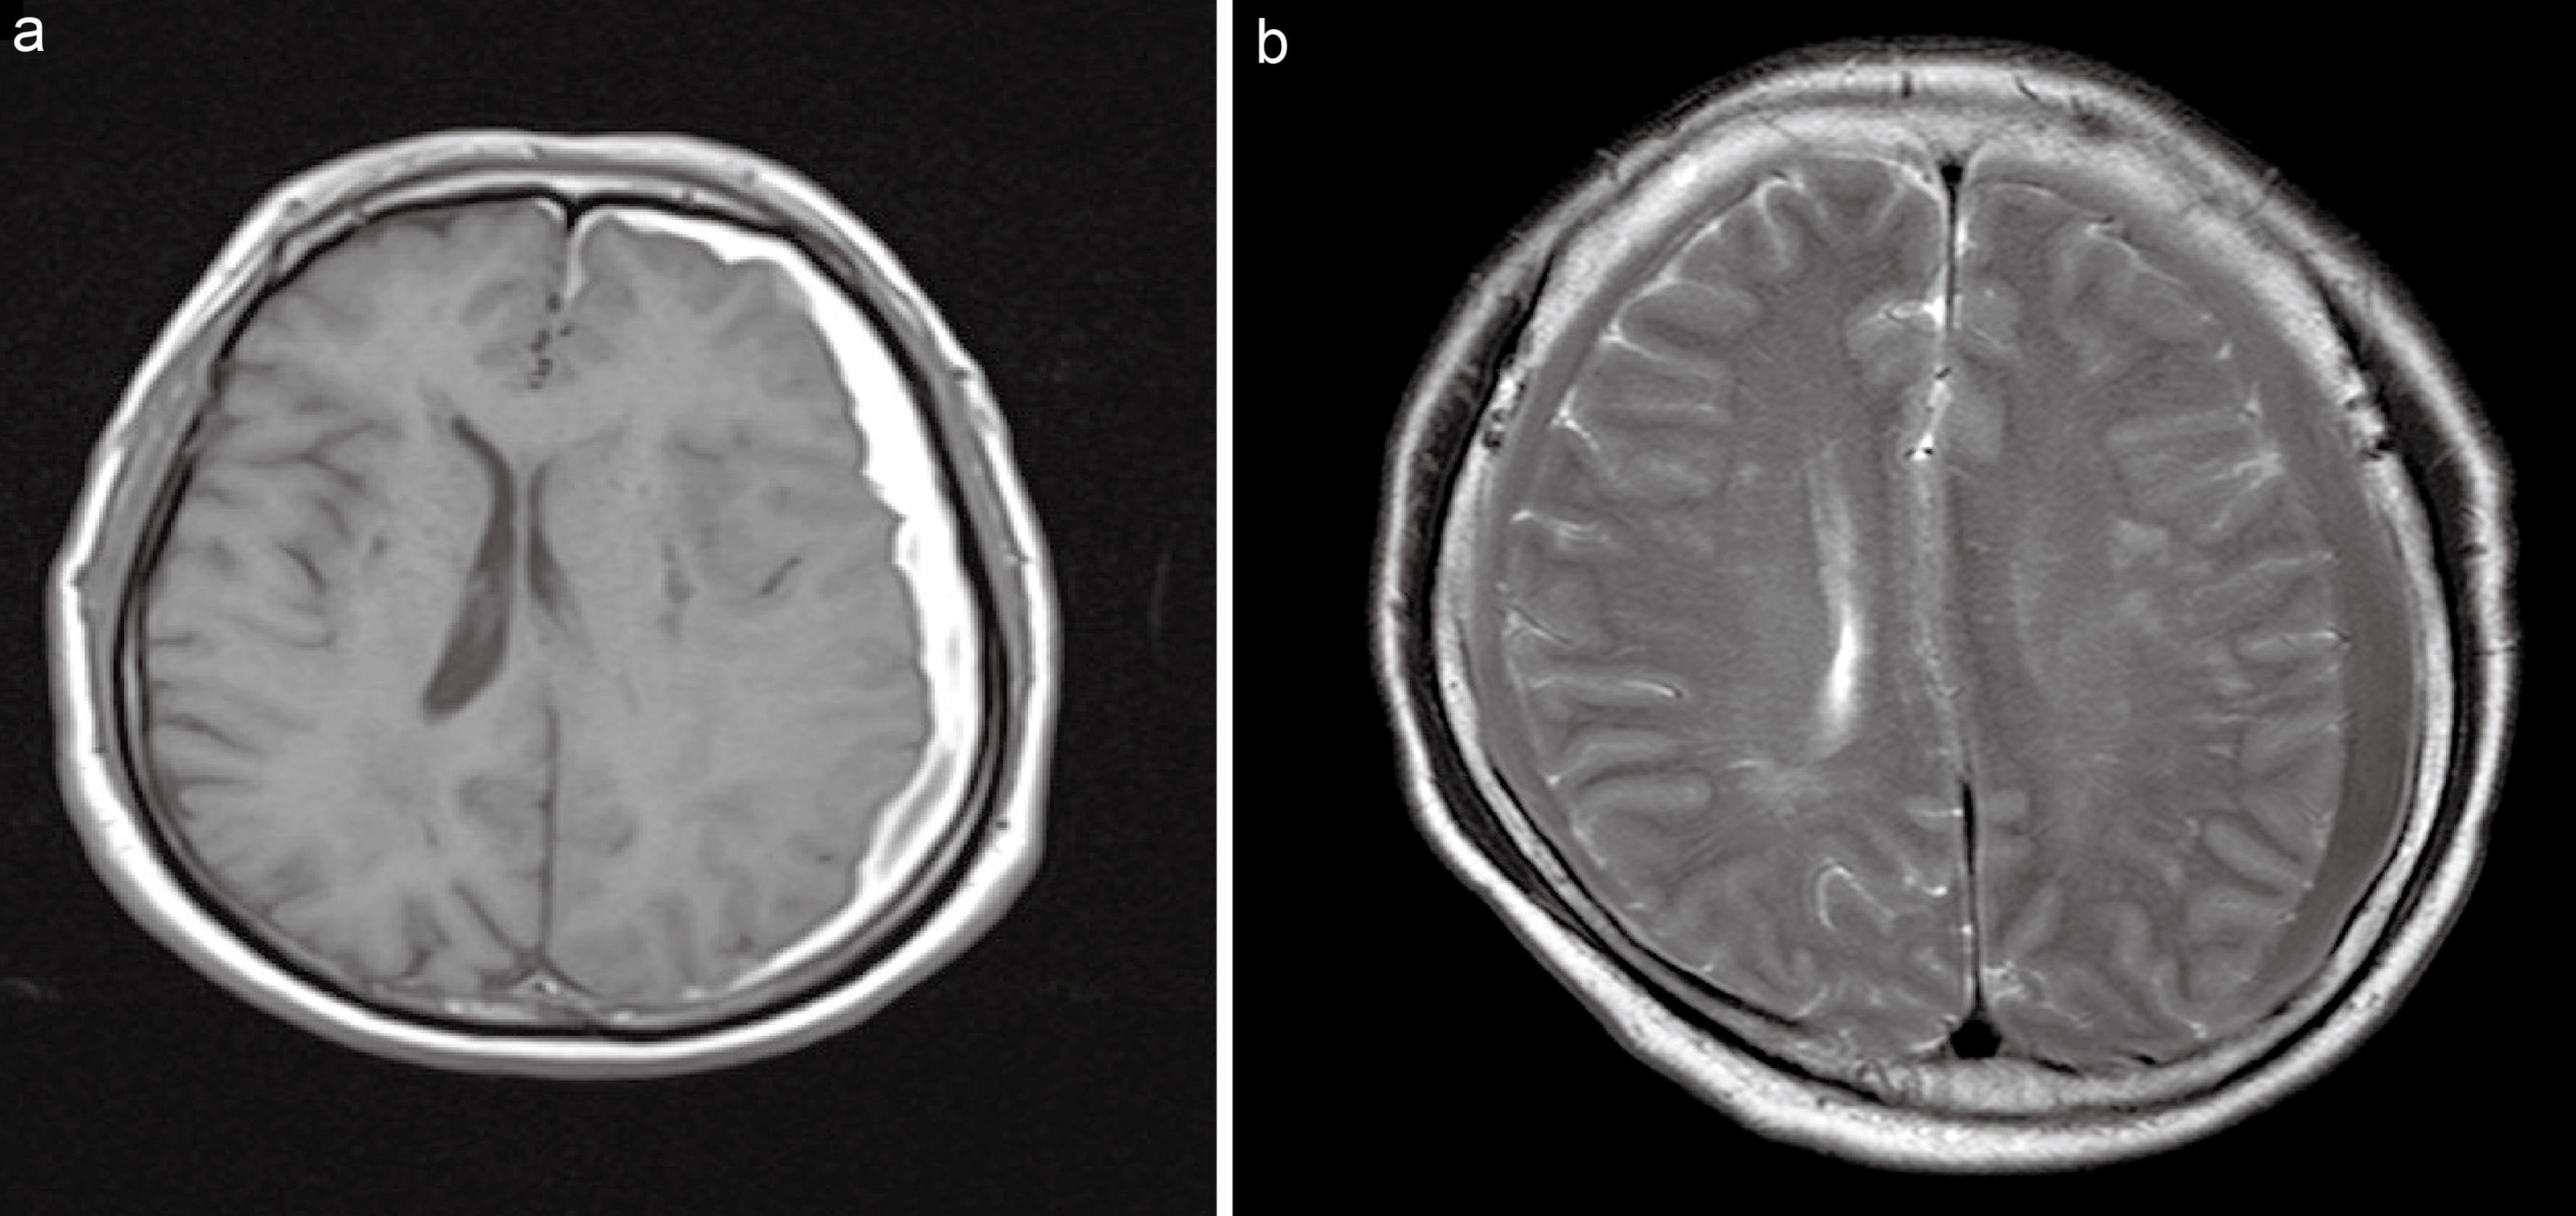

Although CT is the standard diagnostic tool for CSDH, it is often difficult to differentiate the nature of the hematoma and almost impossible to recognize small isodense hematomas.21,22 Compared with CT, magnetic resonance imaging (MRI) can more accurately identify hematomas and their internal structures.22 Meanwhile, MRI can predict the risk of postoperative recurrence by observing structural changes in the reticular appearance of CSDH.23 MRI images of unilateral versus bilateral hematomas are shown in Figure 3.

Magnetic resonance images of chronic subdural hematoma.

Fig. 3  Magnetic resonance images of chronic subdural hematoma.

Unilateral (a) versus bilateral (b) hematomas.